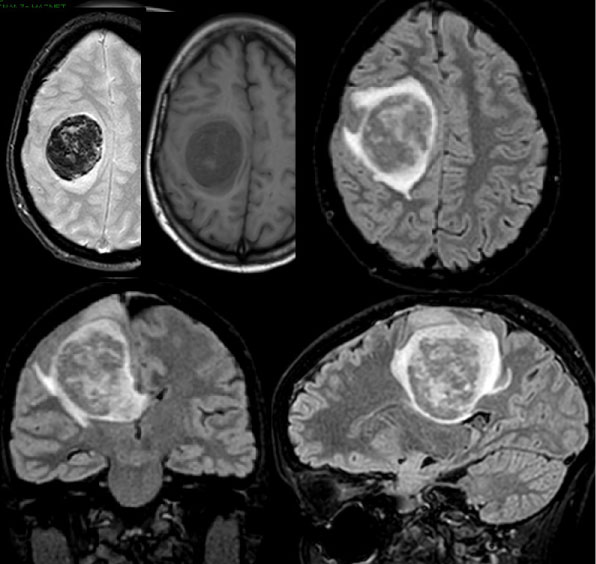

Информация о диссеминированном рассеянном энцефаломиелите